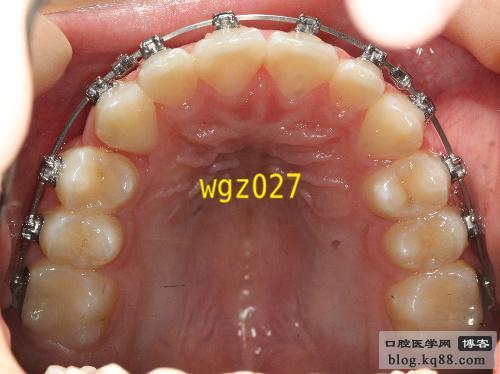

其核心优势在于“低摩擦力自锁技术”,传统托槽依赖结扎丝或橡皮圈固定弓丝,两者间会产生较大摩擦力,牙齿移动需克服阻力,速度较慢;而DamonQ托槽自带微型滑盖式锁扣,无需结扎,弓丝可在托槽内自由滑动,摩擦力降低约60%,牙齿移动更轻柔高效,整体治疗时间可缩短20%-30%,复杂病例(如严重拥挤)的矫正周期也能从2-3年压缩至1.5-2年左右,舒适度方面,传统矫正中结扎丝末端可能刺激口腔黏膜导致溃疡,DamonQ的锁扣设计平滑无尖锐边角,且弓丝滑动时力量更柔和,患者几乎不会感受到明显疼痛或异物感,尤其适合对疼痛敏感的青少年和成人,美观性上,DamonQ提供金属自锁和陶瓷自锁两种材质,陶瓷托槽颜色接近牙齿,表面光滑,佩戴后几乎隐形;托槽体积比传统缩小30%,唇侧厚度减少,对嘴唇压迫感更轻,说话、微笑时更自然,通过持续轻力移动牙齿,DamonQ能更好地维持牙弓形态和咬合关系,减少治疗后复发风险,自锁结构也降低了弓丝脱出概率,避免矫正中断。

DamonQ适用范围广泛,包括青少年恒牙列早期矫正(12-18岁,利用生长发育潜力改善拥挤、龅牙)、成人矫正(对美观和时间有需求的上班族、学生),以及部分复杂错颌畸形(如牙列拥挤、牙间隙过大、龅牙、地包天等),但需注意,严重牙周病患者需先控制牙周炎症,骨量严重不足者需结合正颌手术,具体需医生评估。